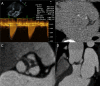

Aortic stenosis and CT calcium scoring: is it for everyone?